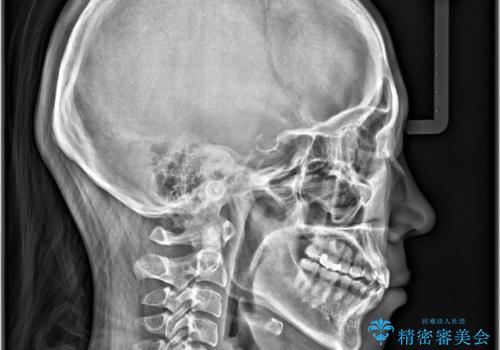

- 歯の捻じれやデコボコを主訴にご来院された患者様です。

矯正治療の精密検査を行った結果、非抜歯(歯を抜かない)矯正治療を選択いたしました。

本症例では、治療の途中で**バイトアップ(咬み合わせを一時的に挙上する処置)**を行い、

上下の歯が干渉しない環境を作りながら、捻転や叢生の改善を進めました。

これにより、歯を無理に動かすことなく、効率的かつ安全に歯列を整えることが可能となります。

その結果、約10ヵ月という比較的短期間で歯列と咬み合わせが整い、機能面・審美面ともに良好な結果を得ることができました。